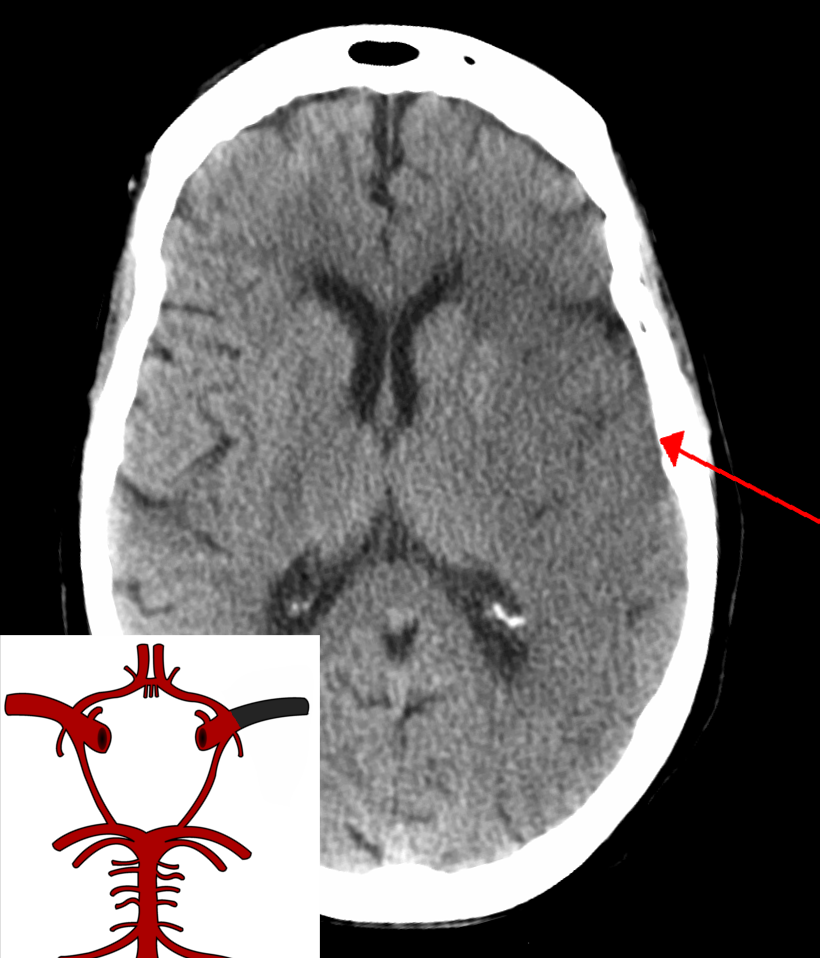

뇌졸중은 신경학적 검사(예: NIHSS) , CT 스캔(대부분 조영제 증강 없이), MRI 스캔, 도플러 초음파, 혈관조영술 등 여러 가지 방법으로 진단한다. 뇌졸중 자체의 진단은 영상 기술의 도움을 받아 임상적으로 이루어지며, 영상 기술은 뇌졸중의 아형과 원인을 결정하는 데에도 도움이 된다.[74] 뇌졸중 진단을 위한 혈액 검사는 아직 일반적이지 않지만, 혈액 검사는 뇌졸중의 원인을 파악하는 데 도움이 될 수 있다.[74] 사망한 사람의 경우 뇌졸중 부검을 통해 뇌졸중 발생 시점과 사망 시점 사이의 시간을 확인할 수 있다.

뇌졸중은 신경학적 검사(예: NIHSS) , 컴퓨터 단층촬영(CT) (대부분 조영제 증강 없이), 자기공명영상(MRI) 스캔, 도플러 초음파, 및 혈관조영술 등 여러 가지 방법으로 진단됩니다. 뇌졸중 자체의 진단은 영상 기술의 도움을 받아 임상적으로 이루어집니다. 영상 기술은 뇌졸중의 아형과 원인을 결정하는 데에도 도움이 됩니다.[74]

응급 상황에서 허혈성 뇌졸중(혈관이 막혀서 발생)과 출혈성 뇌졸중(혈관이 터져서 발생)을 진단하기 위해 CT와 MRI가 사용됩니다.

MRI는 만성 출혈을 감지하는 데 더 민감합니다.[76] CT는 특히 뇌졸중이 작거나, 최근에 발생했거나,[12] 뇌간이나 소뇌 부위(후순환 뇌경색)에 있는 경우 허혈성 뇌졸중을 감지하지 못할 수 있습니다. MRI는 확산 강조 영상을 사용하여 후순환 뇌경색을 감지하는 데 더 효과적입니다.[77] CT는 특정 뇌졸중 모방 질환을 배제하고 출혈을 감지하는 데 더 많이 사용됩니다.[12]